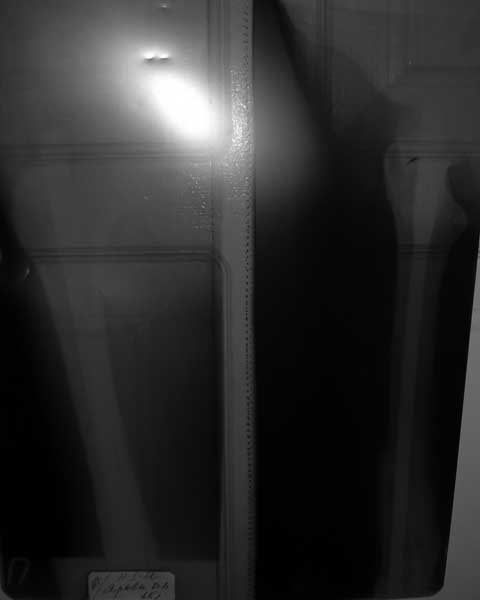

Уважаемые коллеги, поделитесь опытом лечения представленной патологии: Женщина 30 лет,

консолидированный перелом правой бедренной кости после БИОС 2 года назад, укорочение бедра

4 см. Желает восстановить длину сегмента. Стержень разблокирован проксимально и

заблокирован дистально.

Извините за качество снимка